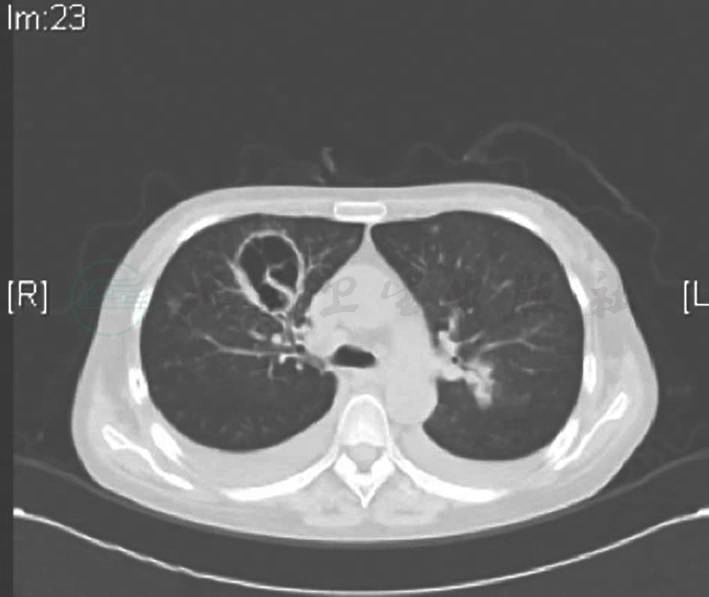

8月23日复查胸部CT(图1):右肺上叶前段空洞融合增大,洞壁增厚,周围新发斑片影、磨玻璃影(感染、出血?),右肺下叶、左肺上叶新发斑片影。肺部病变较前加重。后行多次痰培养,2次真菌培养出根霉属真菌。调整抗生素为哌拉西林钠他唑巴坦钠及两性霉素B脂质体治疗,患者体温正常,咳嗽咳痰减少,水肿减轻,复查CMV DNA转阴,24小时尿蛋白0.92g,复查胸部CT,右肺上叶前段空洞较前明显缩小,洞壁变薄,周围渗出减少(图2)。

图1 两性霉素治疗前